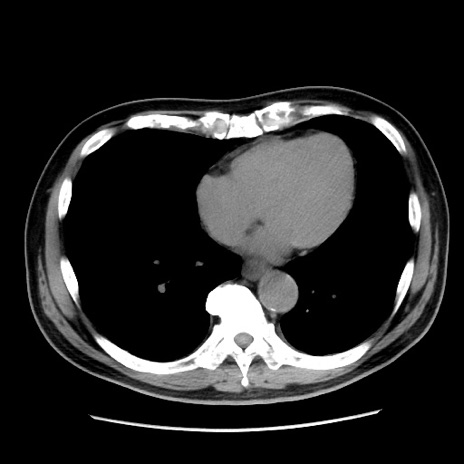

冠状断像